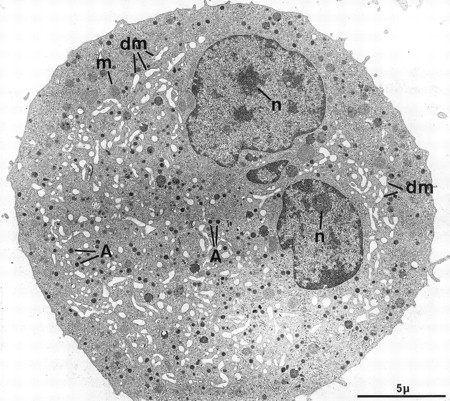

The second population had not been observed by us in any other culture conditions before the use of Mpl-l. It is noteworthy that the described morphologic changes were also present in single cell experiments, ruling out the necessity of other cytokines produced by accessory cells (not shown). A mean of 15% of the MKs had a tighter nucleus with closely apposed nuclear lobes and an indented shape, the chromatin being mostly condensed. The cell surface was uneven, often bristled with thin pseudopods. The appearance of these cells was consistent with their undergoing active platelet shedding. But because electron microscopy takes point-in-time looks at continually changing processes, dynamic relationships could only be inferred from electron microscopic data. Nevertheless, the following morphologic events were observed, leading to the eventual platelet shedding: (1) Alignment and dilatation of the peripheral demarcation membranes (Fig 3a). (2) Unfolding of cytoplasmic sheets and extension of cytoplasmic expansions still attached to the cell body, equivalent to “proplatelets” (Fig 3b). (3) These extensions could be several within a cell, and appeared to be most often still attached to the cell body. (Some large proplatelet-like territories appeared to be separated from the cell core, but this might be an artifact related to the section plan.) The cytoplasmic extensions displayed a beaded appearance, with constriction points separating discrete platelet-like territories. Along a proplatelet, future platelet delimited areas were decreasing from 10 μm to 2 μm in size, the smaller being the furthest from the cell core and the earliest to detach (Fig 4). (4) Careful observation of the constriction zones showed that MK cytoplasmic extensions elongated with the appearance of a central longitudinal bundle of microtubules (Fig 5). Immunogold labeling for tubulin was able to evidence this structure. (5) Some microtubules, transverse to the long axis of the cytoplasmic extension, appeared on both sides of the constriction zone (again confirmed by tubulin immunolabeling); and a central vacuole formed and widened in the constriction zone center, leading to the further detachment of a newly formed platelet (Fig 5). (6) Platelets of various size were found in the supernatant of the culture medium. We have studied this shed platelet population by electron microscopy and immunoelectron microscopy (Fig 6).

Cultured MK grown for 7 days from CD34+CD38+ progenitors in the presence of Mpl-l, and presenting signs of platelet formation. (a) This mature MK displays alignment and dilatation of some peripheral demarcation membranes, individualizing an outer ring of cytoplasm (arrows). (b) The peripheral sheet of cytoplasm has unfolded from the cell core. Constriction zones are regularly disposed along this cytoplasmic extension (arrows).

Sample of cultured MK grown for 7 days from CD34+CD38+ progenitors in the presence of Mpl-l, showing some evidence of platelet formation and shedding. (a) A cytoplasmic process extends straight from the cell core. Constriction zones seem to individualize already distinct platelet fields of large size, close to the MK core (arrows). (b) The appearance of this mature MK is consistent with the process of shedding platelets: The nucleus (N) displays condensed heterochromatin, and its shape is indented. Several platelet-sized cytoplasmic fragments have clearly detached from the MK (P). A large cytoplasmic fragment deprived of nuclear material and possibly corresponding to a detached proplatelet (PP) is also shown. (c) Before releasing platelets, a constriction zone (arrowheads) is formed between the mother cell and the forming platelet (P′). A few detached platelets (P) seem to have already detached, as well as numerous microparticles (arrows). (d) Considerable dilatation of the demarcation membrane system (dm) leads to the demarcation of future platelet fields (P).